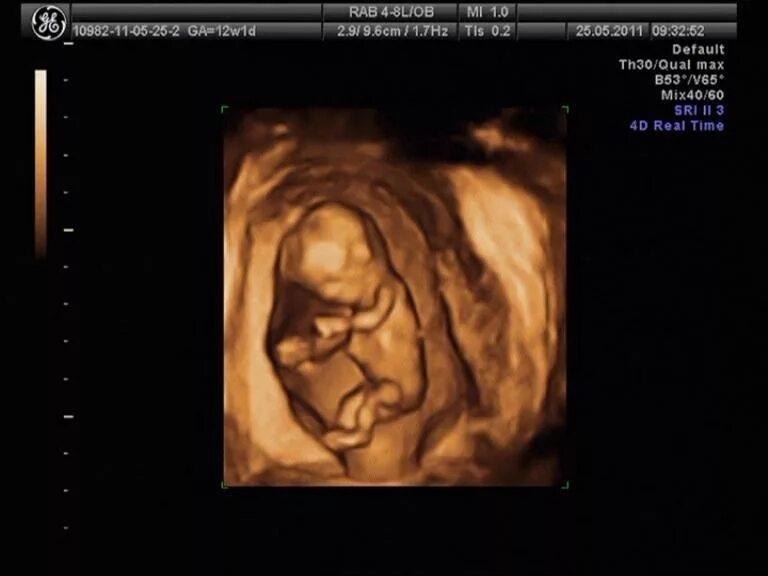

12 недель и два дня